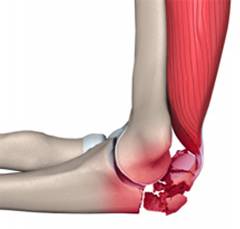

Мышцы и мышечные сухожилия

Мышцы — это анатомические структуры, обеспечивающие движение частей тела. Они состоят из соединенных мышечных клеток и имеют продольную форму, особенно в области локтя, где относятся к скелетным мышцам. Большинство из них имеют два конца, представленные сухожилиями, прикрепляющимися к костям.

Для выполнения функций мышцы должны крепиться к основной кости и к кости, которая будет двигаться. Нормальная нервная иннервация важна для инициации сокращения мышц.

В области локтя прикрепляются мышцы плеча и предплечья. Мышцы плеча отвечают за движения предплечья в локтевом суставе, а мышцы предплечья контролируют движение кисти и вращение предплечья вокруг вертикальной оси. Мышцы делятся на группы в зависимости от расположения и функций.

Эпикондилит — воспаление в точках прикрепления мышц к надмыщелкам плечевой кости. Латеральный эпикондилит возникает при поражении внешнего надмыщелка, медиальный — внутреннего.

Основной симптом — боль вблизи локтевого сустава, возникающая при сгибательных и разгибательных действиях. Боль отсутствует в покое и проявляется при пальпации надмыщелков.

Механизм развития эпикондилита связан с длительными перегрузками лучезапястного сустава.

При эпикондилите поражаются точки прикрепления сухожилий мышц к надмыщелкам плечевой кости. Воспаление может проникать в соседние ткани.